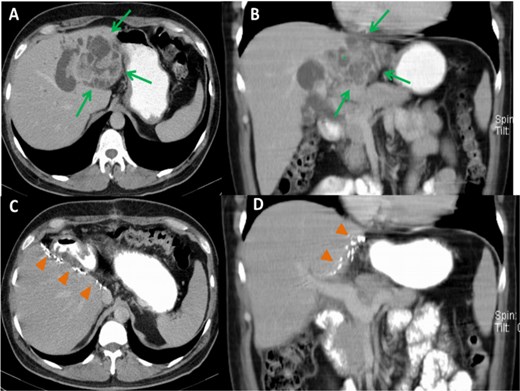

On clinical examination, mild tenderness in the upper abdomen was noted without jaundice or palpable masses. Laboratory investigations, including liver function tests, were within normal ranges, and no evidence of systemic infection was observed. Imaging studies using MRCP and CT demonstrated cystic dilatations of the intrahepatic bile ducts and a 5 cm hypodense lesion in the left hepatic lobe, raising suspicion for malignant transformation (Figs 1 and 2).

Preoperative CT images, axial (A) and coronal (B) planes, show a large, polycystic lesion in the left hepatic lobe (arrows), dilated intrahepatic bile ducts, and the “central dot” sign (*). Postoperative axial (C) and coronal (D) CT images after left hemihepatectomy show no focal lesion in the right hepatic lobe.